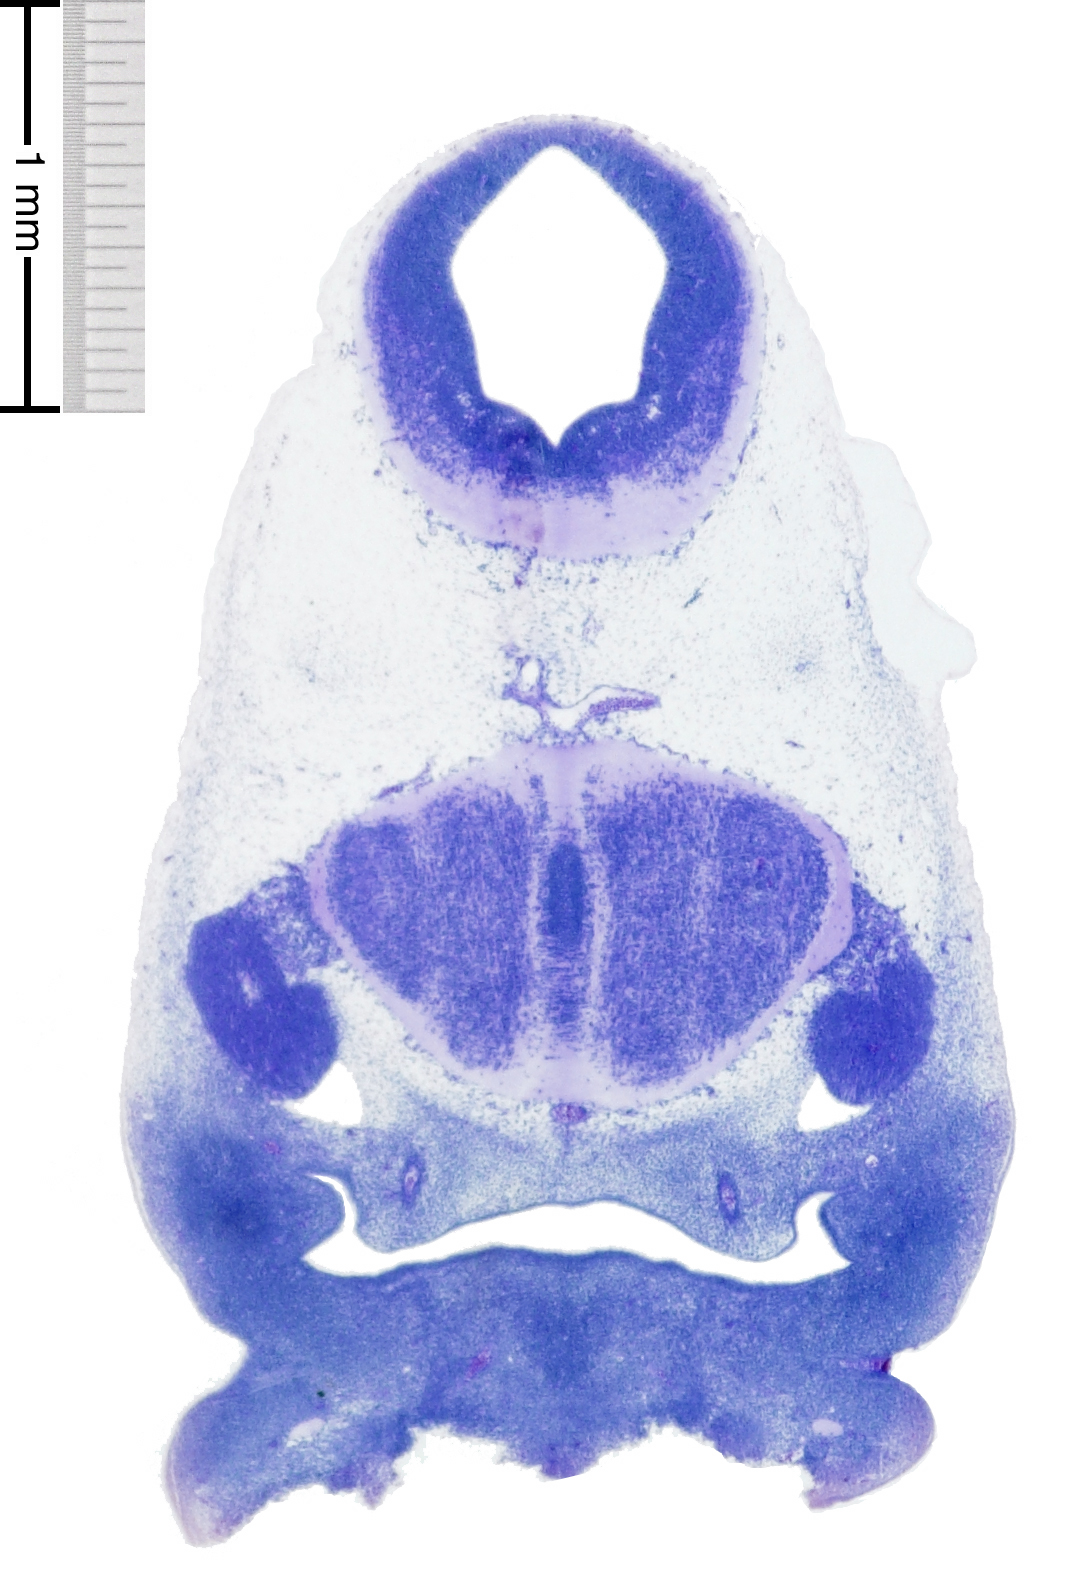

C57BL/6J GD12 Mouse Brain Atlas

Slides from U. Schambra, coronal cuts with slides at every 5th section, with a hematoxylin and eosin (H & E) stain

Currently on section 145.